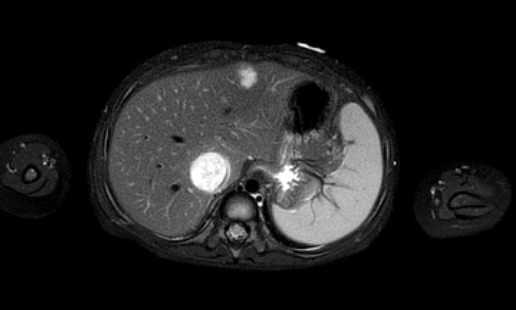

Hình ảnh MRI của một bé gái chín tháng tuổi có khối u ở bụng trái. MRI cho thấy khối u tuyến thượng thận trái, một phần đặc, một phần nang. Có nhiều di căn gan.

Khối u đã được sinh thiết. Có tình trạng chảy máu liên tục qua kim dẫn đường. Vào cuối thủ thuật, hai nút bọt gelatin đã được đặt vào (các dải tăng âm (mũi tên)).